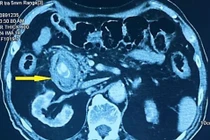

Cụ ông bị tắc ruột do chủ quan sỏi túi mật nhiều năm

Sỏi mật không chỉ gây biến chứng như viêm túi mật, tắc mật do sỏi, viêm tụy cấp... , mà còn có thể gây tắc ruột nên cần phòng ngừa và chữa trị sớm.

Vừa qua, Khoa Cấp cứu tiêu hóa, Bệnh viện Trung ương Quân đội 108 đã tiếp nhận bệnh nhân nam 97 tuổi, tiền sử sỏi túi mật nhiều năm, nhập viện trong tình trạng buồn nôn, nôn liên tục ra dịch tiêu hóa lẫn thức ăn cũ trong vòng 1 tuần.